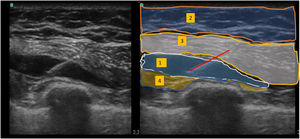

Bloqueo Pecs IILa sonda ecográfica se situó bajo el tercio lateral de la clavícula. Tras localizar la arteria y vena axilares, se movió distalmente la sonda hacia la axila, hasta identificar el músculo pectoral menor, que se utilizó como referencia hasta identificar el músculo serrato anterior al nivel situado entre la 3ª y 4ª costillas. Tras reconocer las estructuras anatómicas adecuadas, se realizó el bloqueo utilizando un abordaje dentro del plano medial-lateral con una aguja de bloqueo de calibre 20. Utilizando hidrodisección salina, se hizo avanzar la aguja al plano tisular entre el músculo pectoral mayor y pectoral menor: se inyectaron 10 mL de ropivacaína al 0,5% (fig. 1). De modo similar, se inyectaron 20 mL de ropivacaína al 0,5% entre el músculo pectoral menor y el músculo serrato anterior (fig. 2).

Se situó la sonda ecográfica a unos 2 cm en paralelo al eje longitudinal del hueso esternón. En primer lugar, identificamos las costillas y la pleura, y en un plano más superficial el músculo pectoral mayor y los músculos intercostales. Se hizo avanzar una aguja de bloqueo de calibre 20 hasta situar la punta en el plano fascial entre el músculo pectoral mayor y los músculos intercostales, inyectándose a continuación 10 mL de ropivacaína al 0,25% (fig. 3).